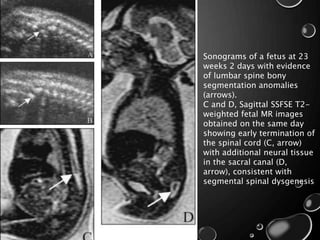

• FETAL MR IMAGING OF THE SPINE IS ALSO HELPFUL IN CASES

IN WHICH A BONY SPINAL ABNORMALITY IS DETECTED ON

PRENATAL SONOGRAPHY.

• IN PARTICULAR, IT CAN BE USED TO DETECT UNDERLYING

SPINAL CORD ANOMALIES, SUCH AS DIASTEMATOMYELIA AND

SEGMENTAL SPINAL DYSGENESIS.

Sonograms of a fetus at 23

weeks 2 days with evidence

of lumbar spine bony

segmentation anomalies

(arrows).

C and D, Sagittal SSFSE T2-

weighted fetal MR images

obtained on the same day

showing early termination of

the spinal cord (C, arrow)

with additional neural tissue

in the sacral canal (D,

arrow), consistent with

segmental spinal dysgenesis

Sonograms of afetus at 23 weeks 2 days with evidence of lumbar spine bony segmentation anomalies (arrows). C and D, Sagittal SSFSE T2- weighted fetal MR images obtained on the same day showing early termination of the spinal cord (C, arrow) with additional neural tissue in the sacral canal (D, arrow), consistent with segmental spinal dysgenesis